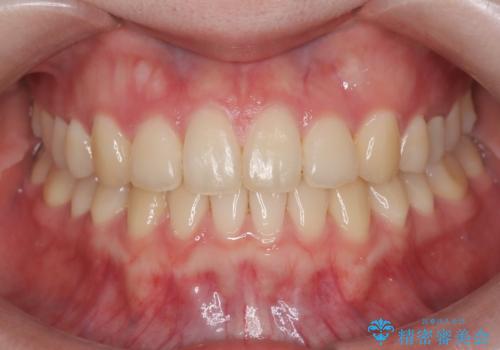

インビザライン(アライナー)矯正とワイヤー矯正のそれぞれの利点を生かした治療を行い、綺麗な歯並びになりました。

歯並びの状態により、最適な矯正方法が異なります。当院では、インビザライン矯正とワイヤー矯正の両方を提供しており、患者様一人ひとりのニーズに合わせた適切な矯正プランをご提案しています。

歯の並びに不安やお悩みを抱えている方は、ぜひご相談ください。インビザライン矯正は透明なマウスピースを使用し、目立たず快適な治療が可能です。一方で、ワイヤー矯正はしっかりと歯を引っ張り、効果的な矯正を行います。

どちらの方法が最適かは、患者様の歯の状態やご希望によって異なります。専門の歯科医師が患者様のお口の状態を丁寧に診断し、適切なアドバイスをさせていただきますので、お気軽にご相談ください。美しい歯並びを実現するために、最適な矯正方法を共に考えましょう。